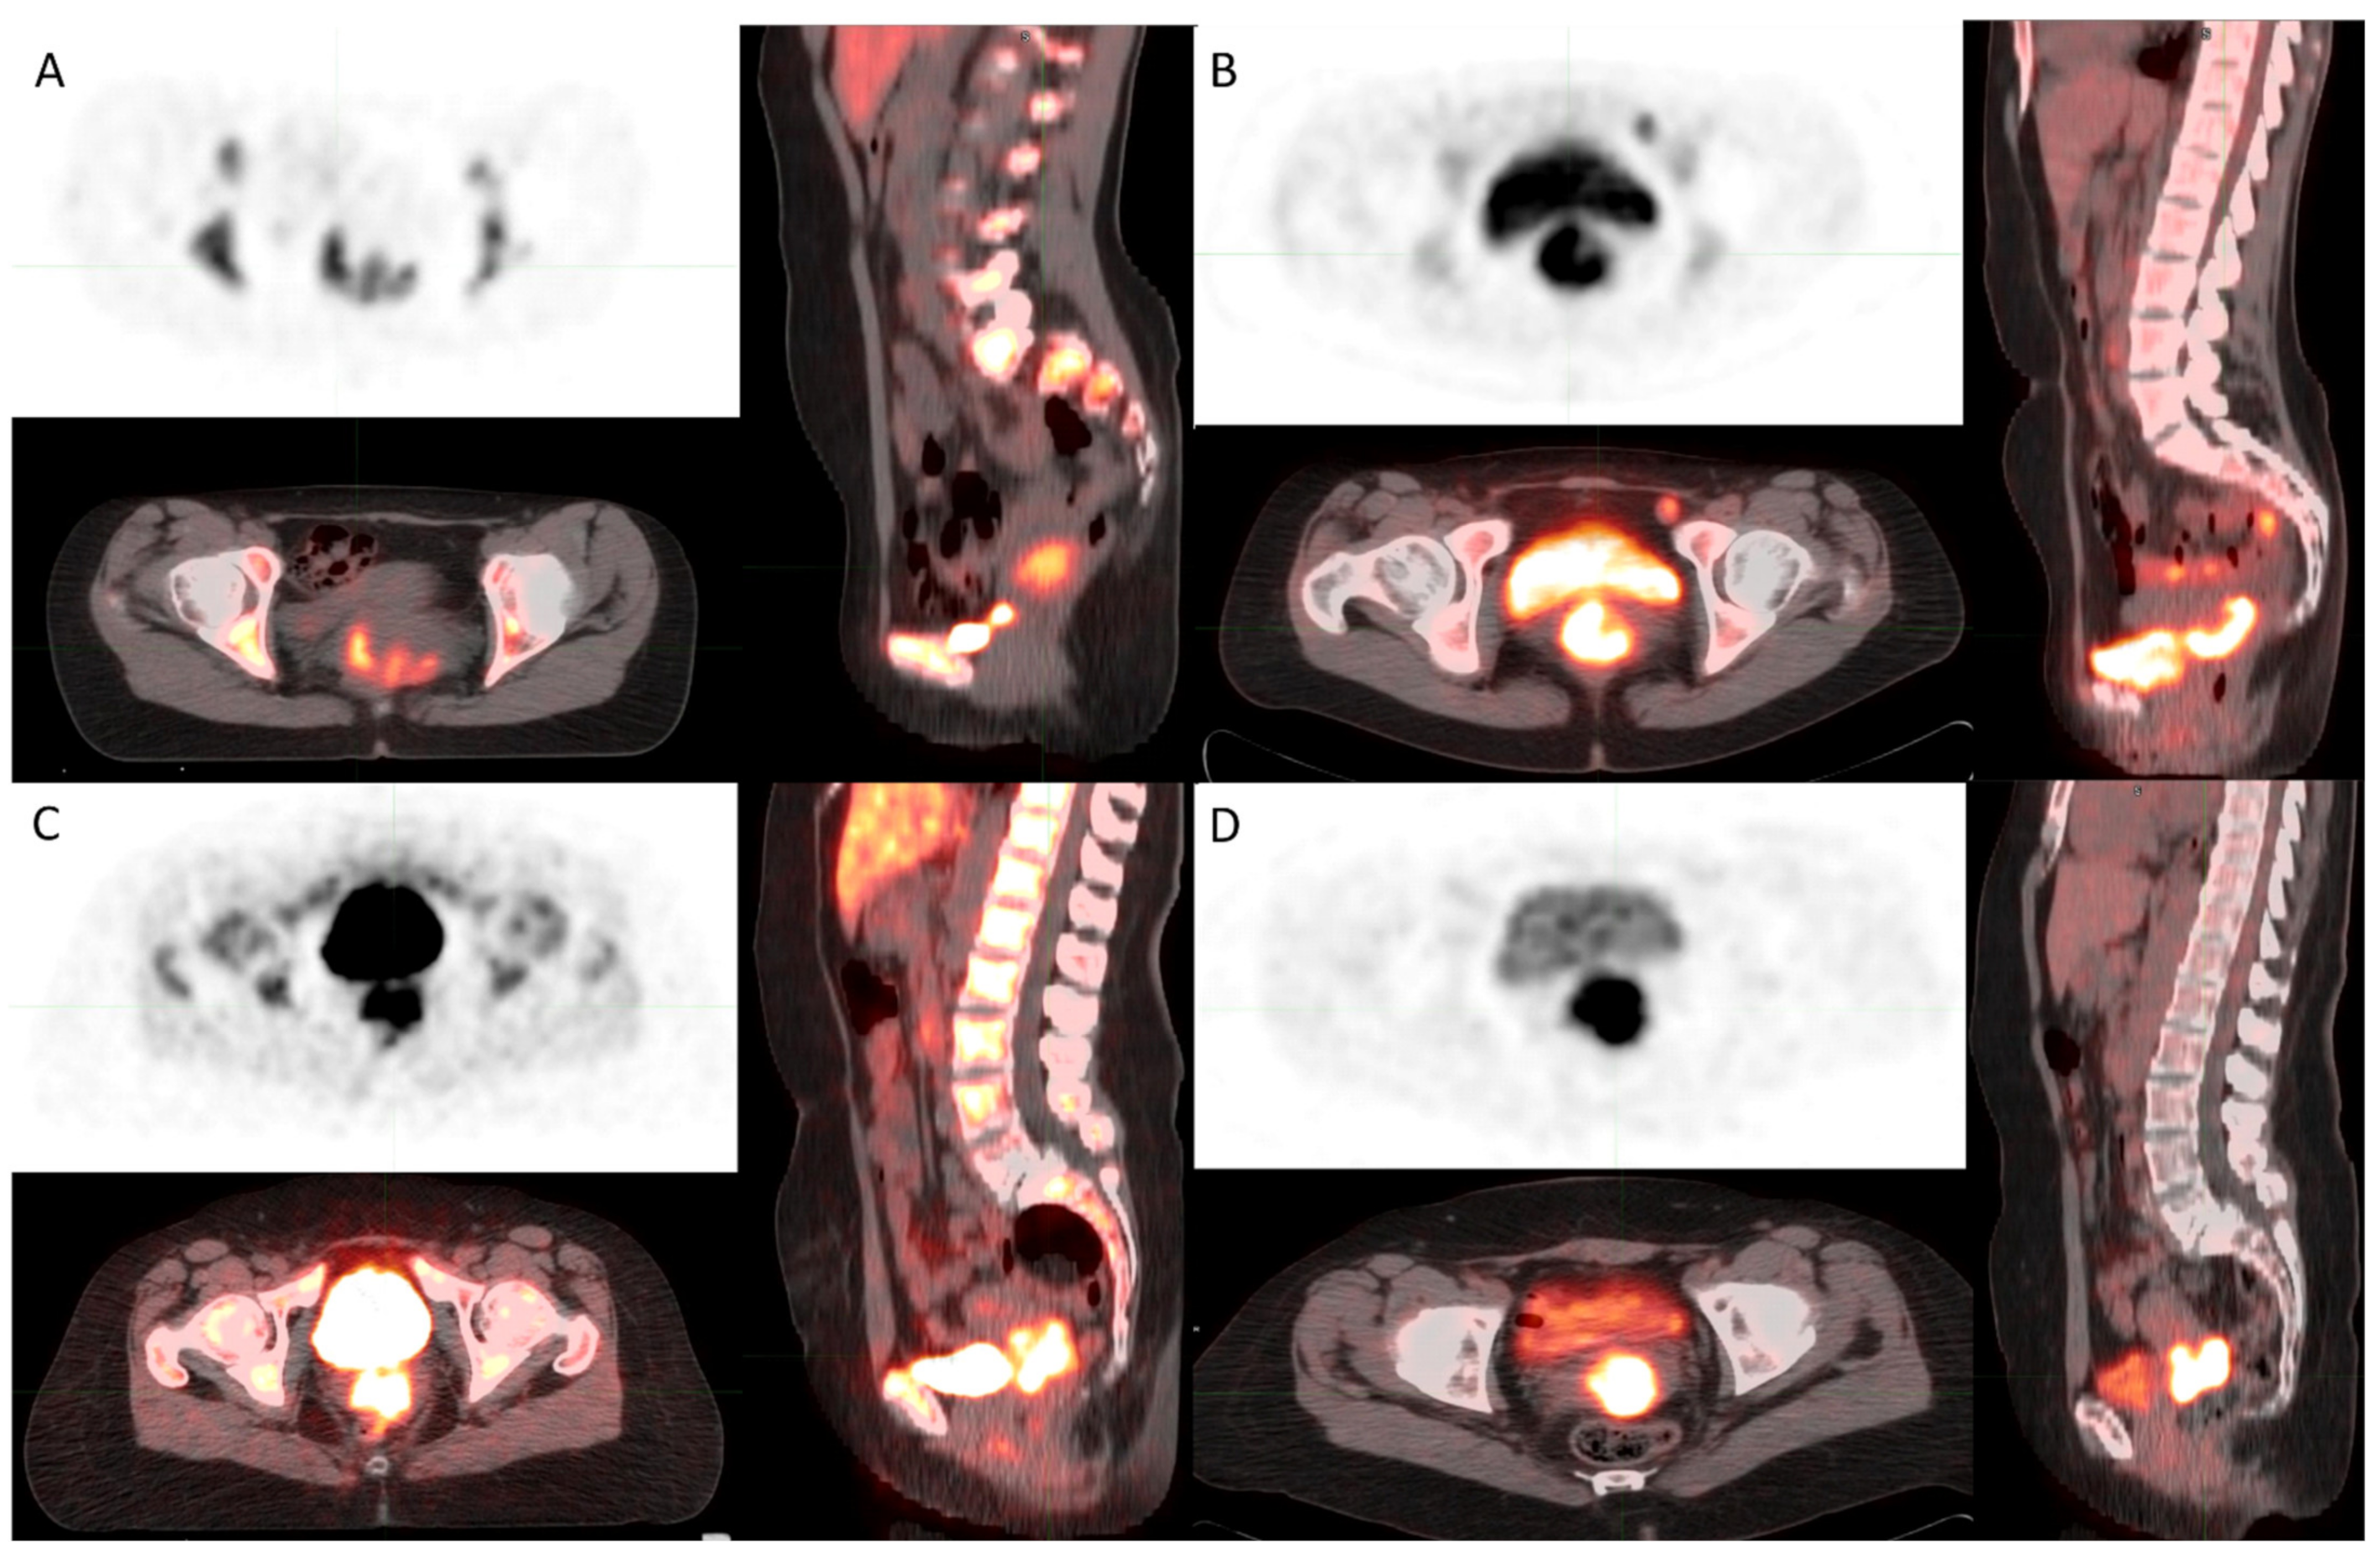

Differences between [18F]FLT and [18F]FDG Uptake in PET/CT Imaging in CC Depend on Vaginal Bacteriology

| SUV max FLT | 34 | 7.7 | 7.46 | 3.1 | 16.5 | 10.7 |

| SUV mean FLT | 34 | 4.8 | 4.4 | 1.9 | 9.9 | 6.8 |

| SUVmin FLT | 34 | 3.2 | 3.5 | 1.3 | 8.9 | 4.6 |

| AUC-CSH FLT | 34 | 0.6 | 0.6 | 0.5 | 0.7 | 0.0 |